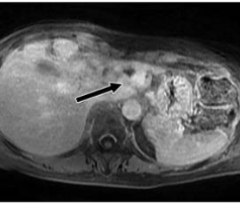

August 9, 2022 — Bot Image, an Omaha-based MRI medical device company has developed an AI-driven medical device CAD ...